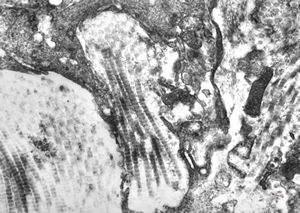

M, 11y. | mycosis fungoides v.s. - cerebriform nucleus of Sézary cell

F, 57y. | mycosis fungoides … cerebriform nucleus of Sézary cell

F, 37y. | mycosis fungoides … cerebriform nucleus of Sézary cell